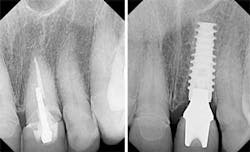

Let’s take a look at a case. Fig. 1 is a pre-op photo of a patient with two all ceramic crowns on teeth numbers 8 and 9 and some veneers. The crown on tooth number 9 is loose and the radiograph in Fig. 2 shows that the tooth has fractured at the gumline. Fig. 3 shows the new implant in place. The dreaded black triangles in Fig. 4 are one of the most challenging esthetic problems dentists deal with. Compare that to the patient’s original pre-op picture in Fig. 1 and you can see why it bothers her.

In addition, food now collects in these areas, and when she speaks she finds herself spitting when she talks, which she has never done before. She both loves and hates her new implant. We treated her with a diode laser (Picasso Lite, AMD Lasers) to loosen the gingival attachment and then placed some dermal filler (Juvederm Ultra Plus XC, Allergan Corporation) into the papilla to rebuild it.

Fig. 5 shows the rebuilt gingival papilla that fills up the black triangles and takes care of her esthetic and functional concerns. The treatment appointment was approximately five minutes, and she can expect this to last for eight months or longer, at which point it will need to be done again. This is a very minimally invasive approach to a very difficult situation and it completely satisfied this patient.